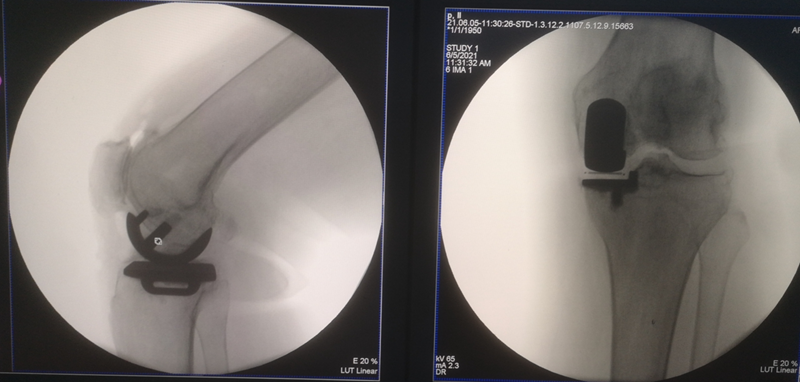

高龄患者内侧单髁置换术

术前

术后检查

对于80岁以上的高龄膝关节骨关节炎患者,准确手术评估、恰当围术期处理、选择微创UKA,不仅有效,而且安全可行。与TKA相比,高龄患者采用UKA治疗不仅有效,还具有并发症少、输血率低、住院时间短、恢复快等特点。但是,高龄膝关节骨关节炎患者通常合并较多内科疾病,围术期科学管理尤为重要。应注意以下几点:术前高血压患者血压应控制在160/90 mm Hg以内;糖尿病患者血糖应控制在10.0 mmol/L以内,尿糖(+++);冠状动脉粥样性硬化病患者适当给予扩张冠脉及营养心肌治疗,超声心动图示左心室射血分数超过 50%以上;心律失常患者完善24 h动态心律检测,必要时请心内科协助诊治;慢性肺部疾病患者肺功能最大通气量超过 60%以上。另外,术前需关注贫血及低蛋白血症情况,必要时给予输血或补充白蛋白治疗。熟练操作、严格微创、减少手术时间及术中出血是手术成功关键。